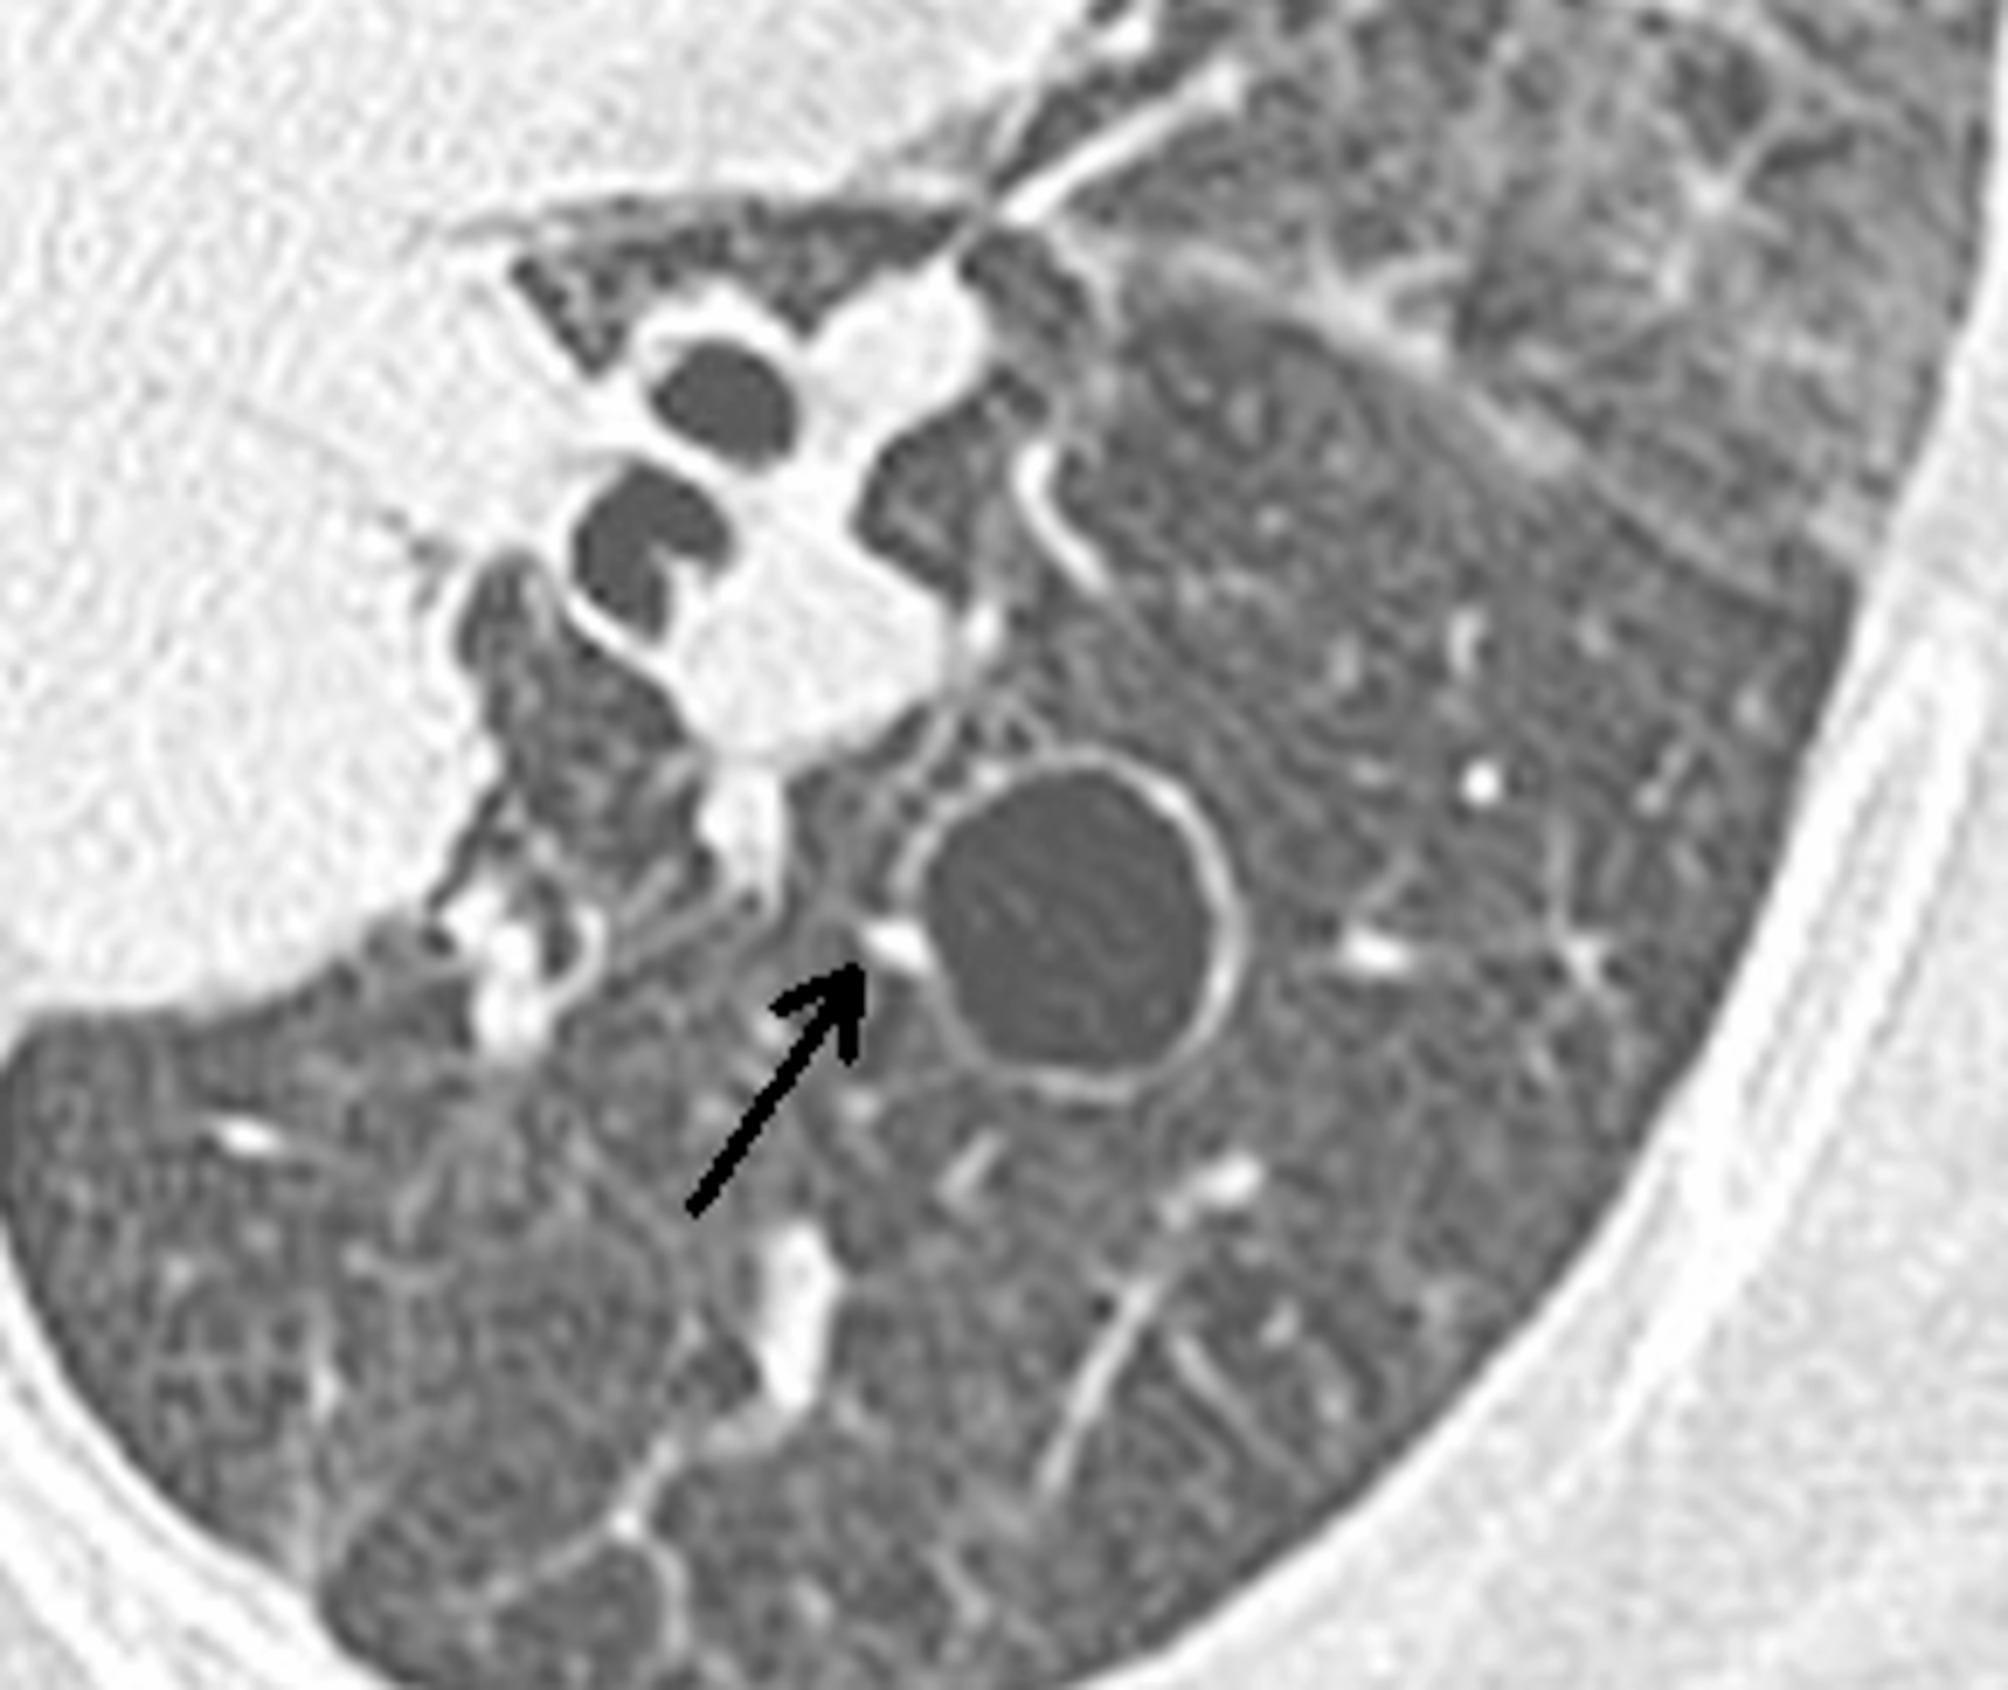

Sjögren's syndrome (SS) is a chronic systemic autoimmune disease mainly involving exocrine glands and particularly affecting the salivary glands and lacrimal glands, thus inducing a dry mouth and dry eyes. Extraglandular organs are also involved in SS, and this results in damage to multiple systems. Among these, lung damage is more common, with high morbidity and mortality rates, and the lack of typical symptoms in the early stages makes it challenging to identify it. The main pulmonary manifestations of SS are bronchitis, pulmonary hypertension, pulmonary cysts, pulmonary amyloidosis, interstitial pneumonia, and pulmonary fibrosis. Cystic lung disease affects about 4-46.2% of patients with SS. The imaging characteristics of pulmonary cysts in SS, including the size, number, morphology, and distribution, as well as differential diagnosis, mechanisms underlying the formation of pulmonary cysts, and current treatment strategies, are presented in this review.